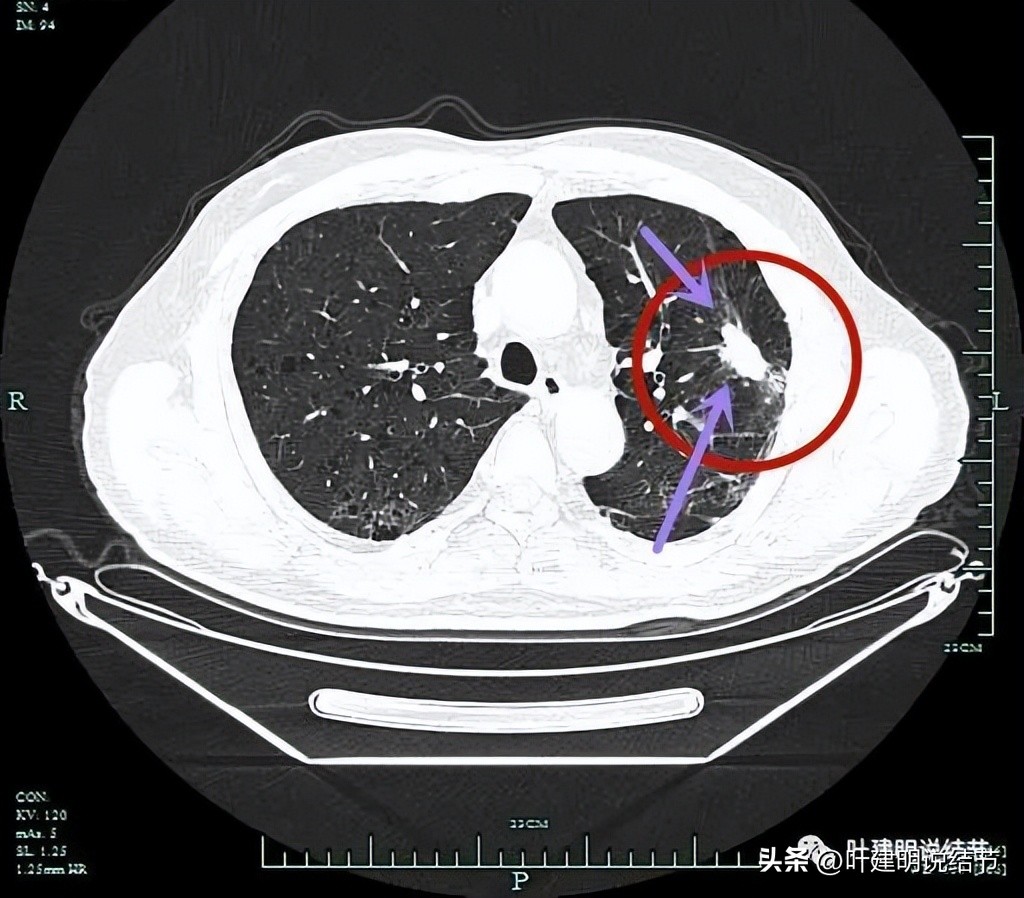

左上病灶开始出现,周围伴慢性炎的表现(红色圈起来部位);其他余部分有多处炎性改变(粉色圈起来的)。

病灶实性,边上条索状并有局灶肺气肿的样子(纹理稀疏)。

病灶实性,有一定膨胀性,表面不平滑。

局部有细毛刺(紫色箭头)。

表面不平,分叶状。